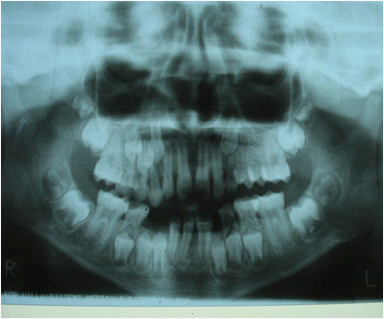

A 10 year old boy reported to the Department of Pedodontics and Preventive Dentistry, Narayana Dental College, Nellore, Andhra Pradesh for routine dental check-up, presented with a large tooth in the lower left front region of the jaw (Figure 1). The boy was not concerned about the aesthetic appearance. The medical and family histories were not significant. Extraoral examination did not show any alterations. Intraoral examination revealed an early mixed dentition period with the presence of one large incisor that was abnormally wide on the left side of the lower arch (Figure 2 and 3). The child had 20 teeth and normal eruption pattern and occlusal status was evident. The double tooth presented a groove upto the cervical third of the crown and hypoplasia on the labial surface (Figure 4). Periapical radiograph displayed the connated incisor with a single root and single pulp canal (Figure 5). The orthopantomograph revealed the presence of double tooth along with the absence of lower left lateral incisor (Figure 6).

Figure 1 Intra oral picture showing teeth in occlusion.

Figure 5 Panoramic radiograph revealed the presence of double teeth and the absence of lower left lateral incisor.